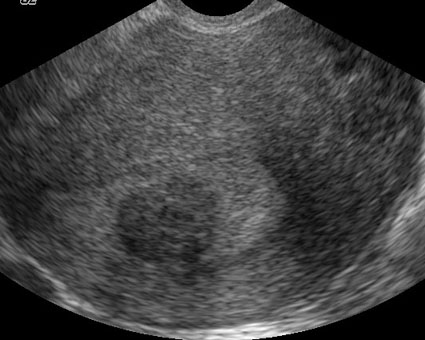

Myome sous-muqueux, arrondi, hypoéchogène par rapport à l’endomètre

(Cliché : Dr. C. TALMANT)